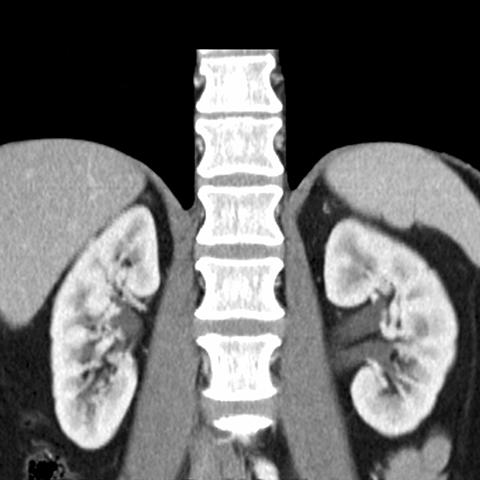

Normal kidneys, CT [7 of 9]